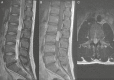

Ependymomas are rare primary central nervous system (CNS) tumors in adults. They occur most commonly in the spinal cord, and have classically been graded histologically into World Health Organization (WHO) grades I, II, or III based on the level of anaplasia. Recent data are showing that genetic heterogeneity occurs within the same histological subgroup and that ependymomas arising from different CNS locations have different molecular signatures. This has renewed interest in developing targeting therapies based on molecular profiles especially given the variable outcomes with radiation and the poor results with cytotoxic agents. In this paper, we present the case of a 46-year-old woman with a classic presentation of spinal cord ependymoma and discuss the current histopathological and molecular classification for ependymomas as well as current guidelines for patient management.